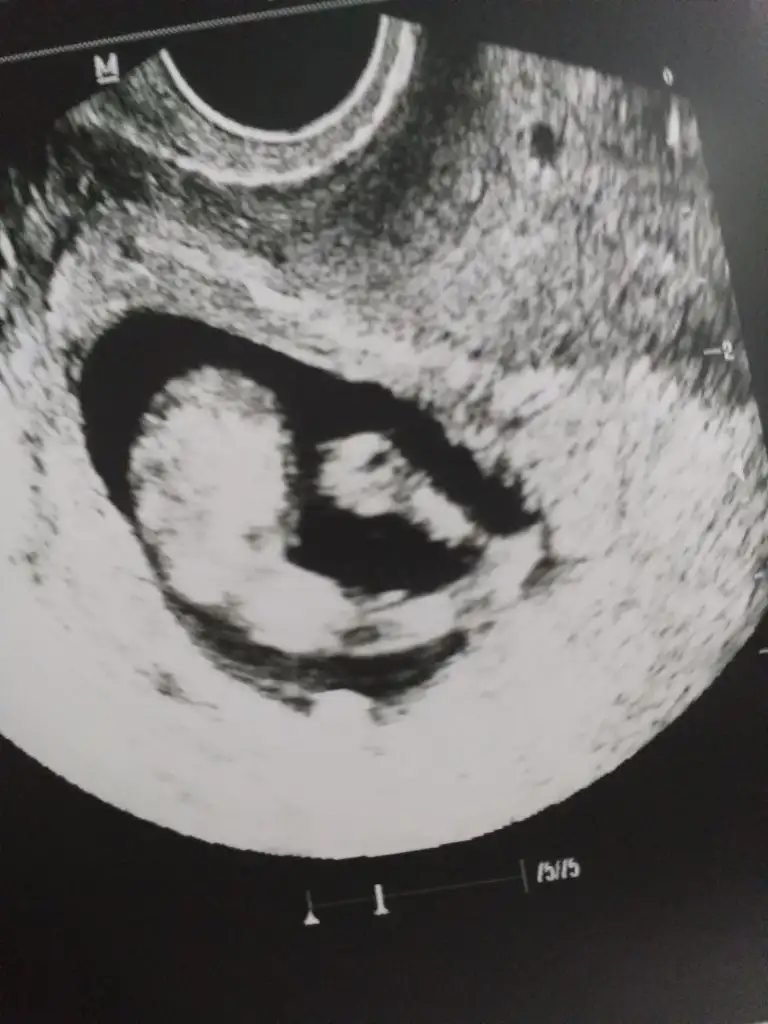

Tamam çok teşekkür ederimmErkek gibi 12+ da paylaşın emin olamadım![]()

Sadece bunlar varNet değil başka usg paylaşım

Kız sanki ama emin olamadım net degil cnm olursa başka usg paylaşınSadece bunlar var

Net çekmeye çalıştım ama burdanmı öle acaba anlamadım saglıklı olsun da ama istedigim de kızKız sanki ama emin olamadım net degil cnm olursa başka usg paylaşın![]()